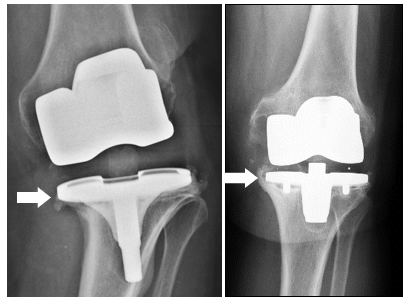

الأسباب الشائعة لاستبدال الركبة الاصطناعية تشمل العدوى، على سبيل المثال عدم الاستقرار أو الألم المستمر.

أثناء عملية جراحية جديدة للركبة، غالبًا ما تكون عمليات زرع خاصة ضرورية لاستبدال الأربطة المعيبة (بما يسمى الأطراف الاصطناعية المزدوجة) أو لإعادة بناء العيوب في العظام (مع زيادات أو مواد بديلة للعظام).